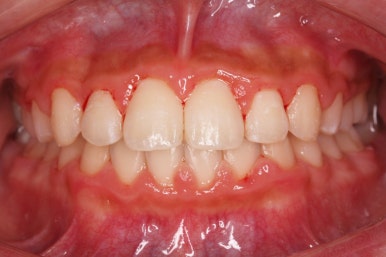

키다리아저씨치과에서 부산비발치교정 전후 사진 비교입니다.

치료 종료 시점에는 위아래 앞니 모두 안쪽에 유지장치를 붙이고 있는 것을 볼 수 있습니다.

교정 중에 양치가 잘 되지 않아 치료 후 모습에서 잇몸이 부어있는 모습도 보이는데 양치질을 잘 해주면 금방 좋아질 수 있습니다.

앞니가 매우 가지런해졌고 예뻐졌네요.

삐뚤했었던 특히 안으로 쏙 들어가 있었던 작은 앞니가 개선되면서 웃는 모습이 많이 좋아졌습니다. 상대적으로 덧니처럼 보이던 송곳니의 느낌도 좋아졌네요.

부산비발치교정으로 했음에도 입이 더 튀어나오거나 하지 않았습니다.